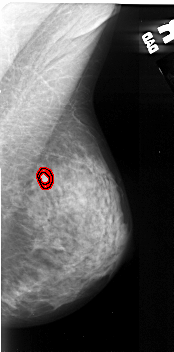

A_1057_1.RIGHT_MLO

RIGHT_CC LINES 4441 PIXELS_PER_LINE 2206 BITS_PER_PIXEL 16 RESOLUTION 42 OVERLAY

FILE: A_1057_1.RIGHT_CC.OVERLAY

TOTAL_ABNORMALITIES 1

ABNORMALITY 1

LESION_TYPE MASS SHAPE OVAL MARGINS ILL_DEFINED

ASSESSMENT 4

SUBTLETY 4

PATHOLOGY MALIGNANT

TOTAL_OUTLINES 1

BOUNDARY